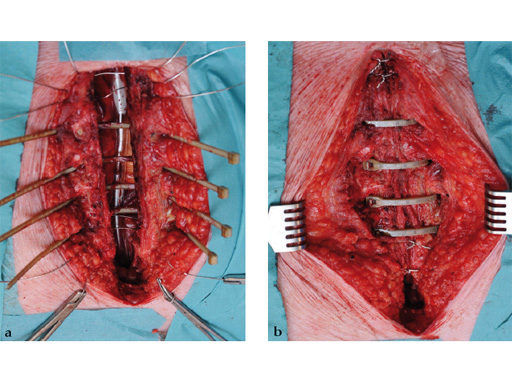

The sternal zipfix system primarily consists of polyetheretherketone (PEEK), biocompatible implants, which are similar to cable ties, and an application instrument. The purpose of this system is to achieve sternal closure following sternotomy by stabilizing the sternum and promoting fusion.

The implant itself comprises a removable stainless steel needle for peristernal application, the body with a ratchet mechanism, and a flat locking head. The application instrument is used to tension the implant, without overtensioning it, and also to cut it.

The hybrid sternal closure technique with stainless steel wires and sternal Zipfix has been used in the authors' institution in 50 patients without any instance of sternal instability or dehiscence.

The patient was morbidly obese with a BMI of 45. Due to the high risk for sternal instability and/or deep sternal wound infection, closure was performed using the sternal zipfix system. The zipfix provides quick and reliable stable fixation of the sternum even in patients that are at a higher risk to develop a sternal instability or a deep sternal wound infection.